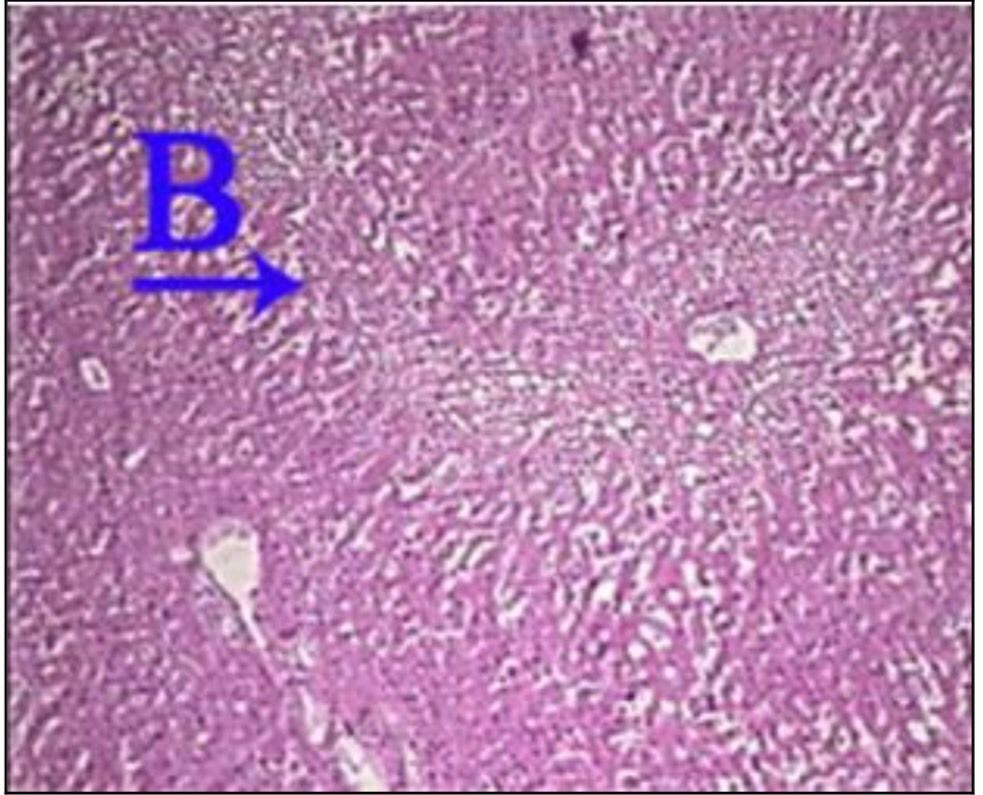

What is the correct answer at point B?

• - travées de sclérose annulaire

• - nodule cirrhotique, sans veine Centro lobulaire

• - néoformation canalicule biliaire

• - infiltration lymphocytaire

• - hépatocyte contenant de la bile